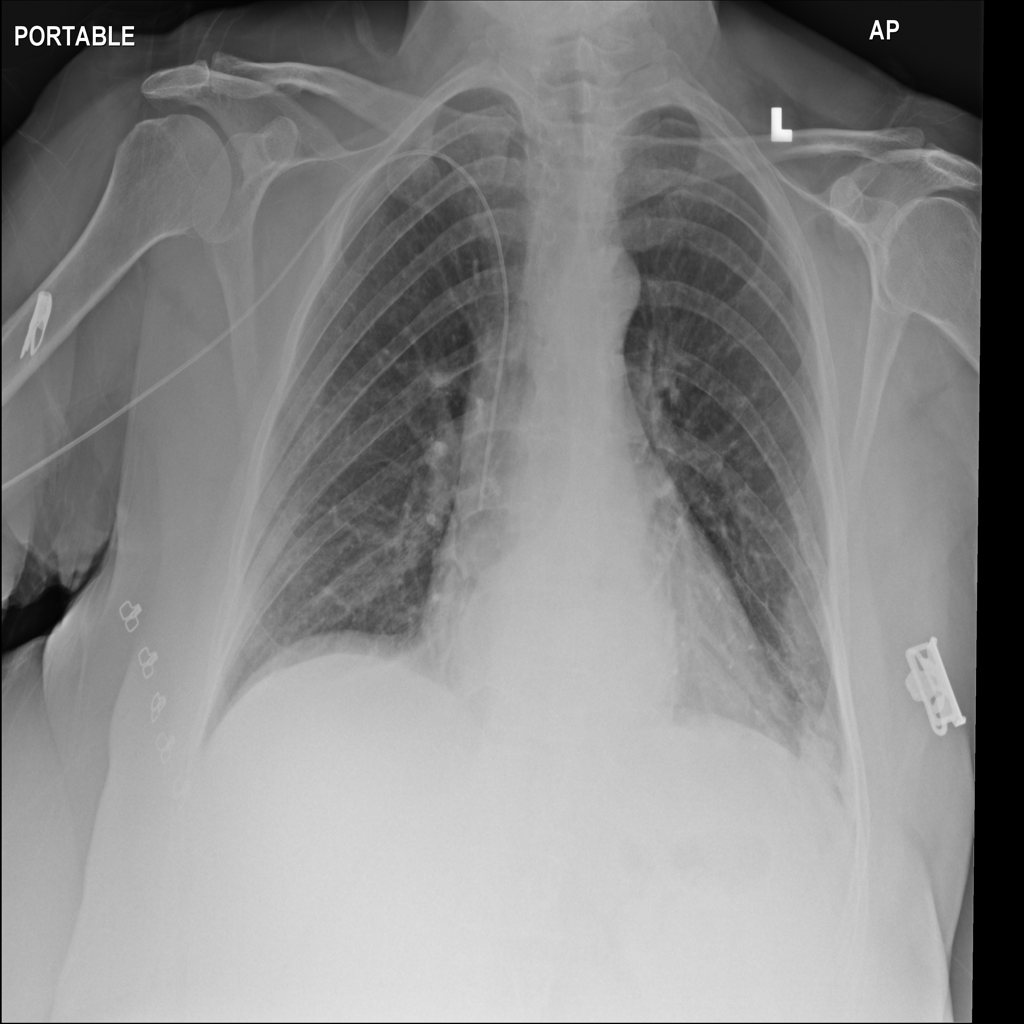

PAT-717B · IMG-008Hernia

PAT-717B · IMG-008

PA